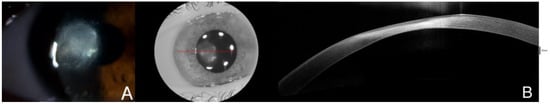

(A). Clinical evolution with endothelial infiltrates and expansion of the infiltrate, as well as corneal necrosis hyperreflective in AS-OCT, with small cystic spaces next to the epithelium. The initial culture from the corneal sample returned positive for Streptococcus oralis resistant to eritromicine, clindamicine and tetracycline. Due to these results and a torpid clinical course without symptomatic improvement, appearance of endothelial deposits and impairment of stromal edema in AS-OCT with hyperreflectivity reaching deeper layers (B) and BCVA loss to 0.3, the treatment was updated with interruption of the fortified topical antibiotics, which were switched to moxifloxacin and linezolid. Natamicyn was added to the treatment in substitution of voriconazole. Two days later, the endothelial deposits disappeared and the patient related symptomatic improvement, but a week after, the BCVA in the right eye was severely reduced to 0.05. The red line is correspondene of the en face picture with the selected section on the AS-OCT.